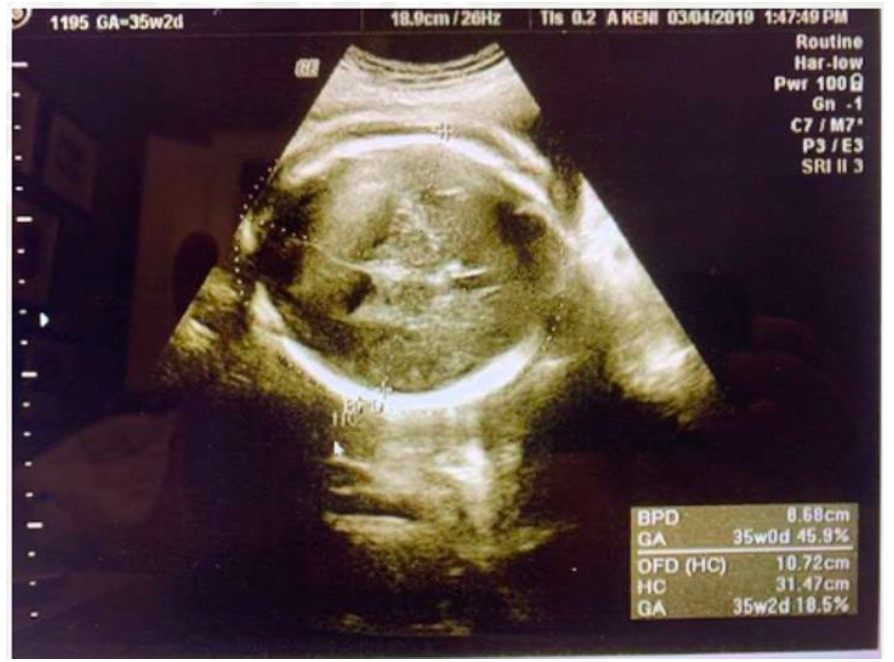

When absent fetal heart tones in this pregnancy were discovered, ultrasound also revealed edema around the fetus’s brain (Figure 2) and diaphragm (Figure 3), indicating hydrops fetalis. The fetus still showed to be in a vertex position with a normal amount of amniotic fluid upon further assessment. The patient was sent to labor and delivery where she was induced and given an epidural. She had a spontaneous vaginal delivery that produced a 5 lb 13 oz stillborn female at 35 weeks, 3 days. The placenta was sent to pathology for further assessment.